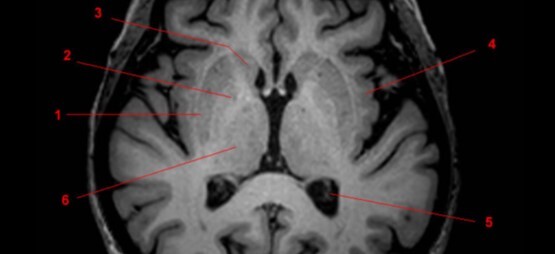

Label 1-5

Label 1-6

1=Frontal bone

2-Falx cerebri

3-Left frontal lobe

4-Left anterior cerebral artery

5-Right temporal lobe

6-Temporal horn of left lateral ventricle

Label 7-11

7=Basilar artery

8-Right posterior cerebral artery

9-Internal occipital protuberance

10-Midbrain

11-4th ventricle